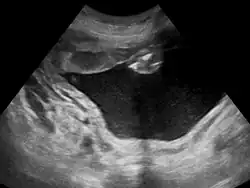

Polyhydramnios is a medical condition describing an excess of amniotic fluid in the amniotic sac. It is seen in about 1% of pregnancies.[1][2][3] It is typically diagnosed when the amniotic fluid index (AFI) is greater than 24 cm.[4][5] There are two clinical varieties of polyhydramnios: chronic polyhydramnios where excess amniotic fluid accumulates gradually, and acute polyhydramnios where excess amniotic fluid collects rapidly.